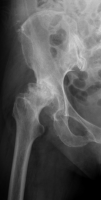

回忆起患者刚来南海医院脊柱关节外科时的情形,科室主任张毅介绍,患者股骨头严重坏死、脱位,且髋臼有一大块缺损,患肢短缩超过2厘米、关节囊挛缩、明显畸形,患者病情重、病程长、髋关节活动严重受限。如果想要从根本上解决患者病痛,提高患者的生活质量,必须行手术治疗。但这将是一例高难度、操作复杂的髋关节置换术病例。

但传统X线、CT、MRI等检查在了解髋臼缺损方面不够全面、精准、直观,在手术方案确定和假体选择上都给医生出了难题。为此,大家决定借助“神器”3D打印技术,以1:1再现患者的病患髋关节,以便精准制定手术方案。与此同时,项目组成员迅速联系影像中心获取了患髋CT数据并使用MIMICS软件重建患髋三维图像并使用3D打印技术1:1再现患者的髋关节,根据髋关节模型,项目组再次详细致地讨论了手术方案,并在术前与患者及其家属通过3D模型直观的介绍患者的病变以及手术的方案,获得了患者及家属的理解和支持。

术前